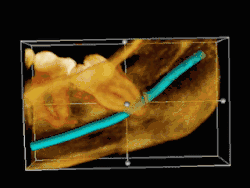

Die folgenden Röntgenbilder sind Ausschnitte aus Orthopantomogrammen (OPG):

Weisheitszahn 38; fast bis zur Kauebene durchgebrochen; distale Wand vollständig im Knochen; voll ausgebildete Wurzel; Wurzelspitzen projizieren sich auf den Nervus alveolaris inferior